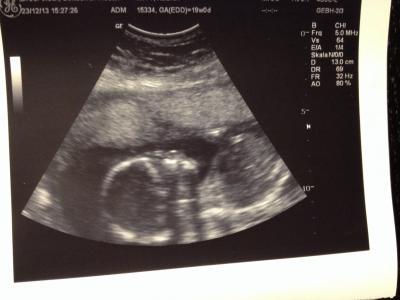

Hallo ihr Lieben! Heute war es endlich soweit und ich durfte endlich wieder zum Ultraschall! Wir haben ein Outing bekommen: es wird ein kleiner Bub! Der kleine Zwerg wiegt 346,7g und es ist alles dran und altersgemäß entwickelt! Und zusätzlich zu all dem bin ich heute noch in die 20.SSW gekugelt! :) Ich wünsche euch allen schöne Weihnachten im Kreise euer Familie!

Bild zu 20.SSW - Forum für Mai - Mamis